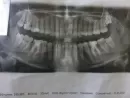

Пошла в стоматологию на диагностику. Пломбам многим от 7-16 лет. Думала, скажут менять. В принципе так и сказали. Но ещё сказали удалять зуб мудрости, который только вылез. Удалять якобы из-за того, что мало места, и он начнёт двигать другие зубы.

У меня треснула 7-ка и отвалилась стенка, стоящая с 8-ой. Сказали, скорее всего, из-за зуба мудрости. Поэтому его надо удалять, а потом лечить 7-ку.

Да, действительно зуб "мудрости" подлежит удалению. Ему не хватает места в зубной дуге, вследствие чего начнёт двигать зубной ряд. Возможно, начнётся смещение зубов.

Функции этот зуб не несёт. Лучше 8-ой зуб удалить.